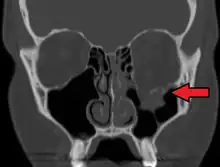

FractLeftOrbitFloorMark

orbital blowout fracture demonstrating enophthalmos